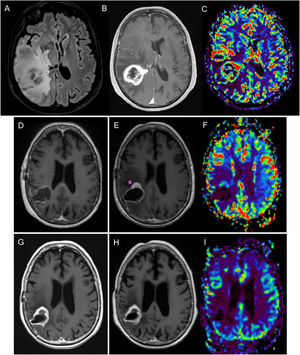

Figure 3.76-year-old woman diagnosed with right parietal glioblastoma demonstrated on MRI with FLAIR sequences, post-contrast T1 and CBV mapping in DSC perfusion (A–C). Complete resection of the contrast-enhancing component in the 24-h postoperative MRI (D). In the post-radiotherapy MRI (E,F), corresponding to the baseline MRI, there is a parietal nodular area of contrast enhancement (asterisk) without significant increase in volume in the CBV mapping of the DSC perfusion study (F). In the subsequent scans, six weeks (G) and 12 weeks post-concomitant RT and CT (H, I), a reduction in the size of the area of enhancement can be seen, without an increase in volume (I), findings related to pseudoprogression.

CBV: cerebral blood volume; DSC: dynamic magnetic susceptibility testing; MRI: magnetic resonance imaging.

Diagnostic MRI with FLAIR (A) and post-contrast T1-weighted (B) sequences of glioblastoma in the right frontal-parietal region in a 39-year-old male. The post-radiotherapy MRI corresponding to the baseline MRI (C–E) shows a frontal-parietal area with altered FLAIR signal (C) and a contrast-enhancing component (D), with a slight focal increase in the volume in the CBV mapping (arrow) in the DSC perfusion study (E). In the 1st follow-up MRI three months post-concomitant RT and CT (F–H), disease progression is evident, with the finding of an increase of >25% in the contrast-enhancing component (G), which correlates with areas of increased perfusion volume (circle). Additionally, there is a non-measurable uptake component which also shows an increase in volume (arrowheads). Further follow-up MRI (I–K) after the start of bevacizumab shows antiangiogenic agent-related changes in the form of a reduction in the area of signal abnormalities in FLAIR sequences with improvement of the mass effect (I), reduction in the size of the area of contrast enhancement (J) and a tendency towards a return to normal of the volume map (K).

CBV: cerebral blood volume; DSC: dynamic susceptibility contrast magnetic resonance perfusion; MRI: magnetic resonance imaging.

Dynamic susceptibility contrast (DSC) magnetic resonance perfusion has proved to be useful in differentiating between post-treatment changes and tumour recurrence, with relative volume being the most consistent parameter13 (Figs. 3 and 5). A consensus of technical and post-processing parameters for DSC perfusion was recently published57 which could be included within the BTIP.